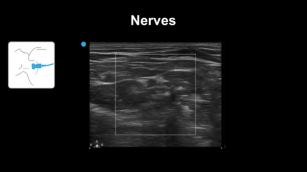

Identifying structures of the neck using ultrasound. 28th Nov 2017 - Sara Damewood, MD [VIDEO 7:58] Learn how to differentiate between various structures of the neck with the help of ...